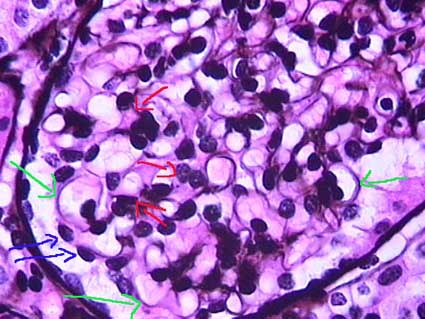

The glomerular tuft is formed by lobules of capillaries. The afferent arteriole gives origin to 4 - 8 capillaries, each one of which is subdivided to form a lobule. In each lobule there are several mesangial areas: the portion of mesangium that support several capillaries. It is very important to recognize the mesangial areas to determine when there is or non hypercellularity: cluster of three or more nuclei per mesangial area in thin 2 to 3 micron sections away from the vascular pole (Figure2 and Figure 3).

Figure 2. The lobules appear highlighted in red; in normal glomeruli is difficult to determine with precision its limit. Within each lobe there are several mesangial areas (some of them indicated with green arrows) in which there are not more than 2 or 3 nuclei of cells (Masson’s trichrome, X300).

Figure 3. In this image of a lobule of the glomerular tuft, the red arrows indicate several mesangial areas in which there are 1 or 2 nuclei. The green arrows indicate nuclei of endothelial cells (Masson’s trichrome, X400).